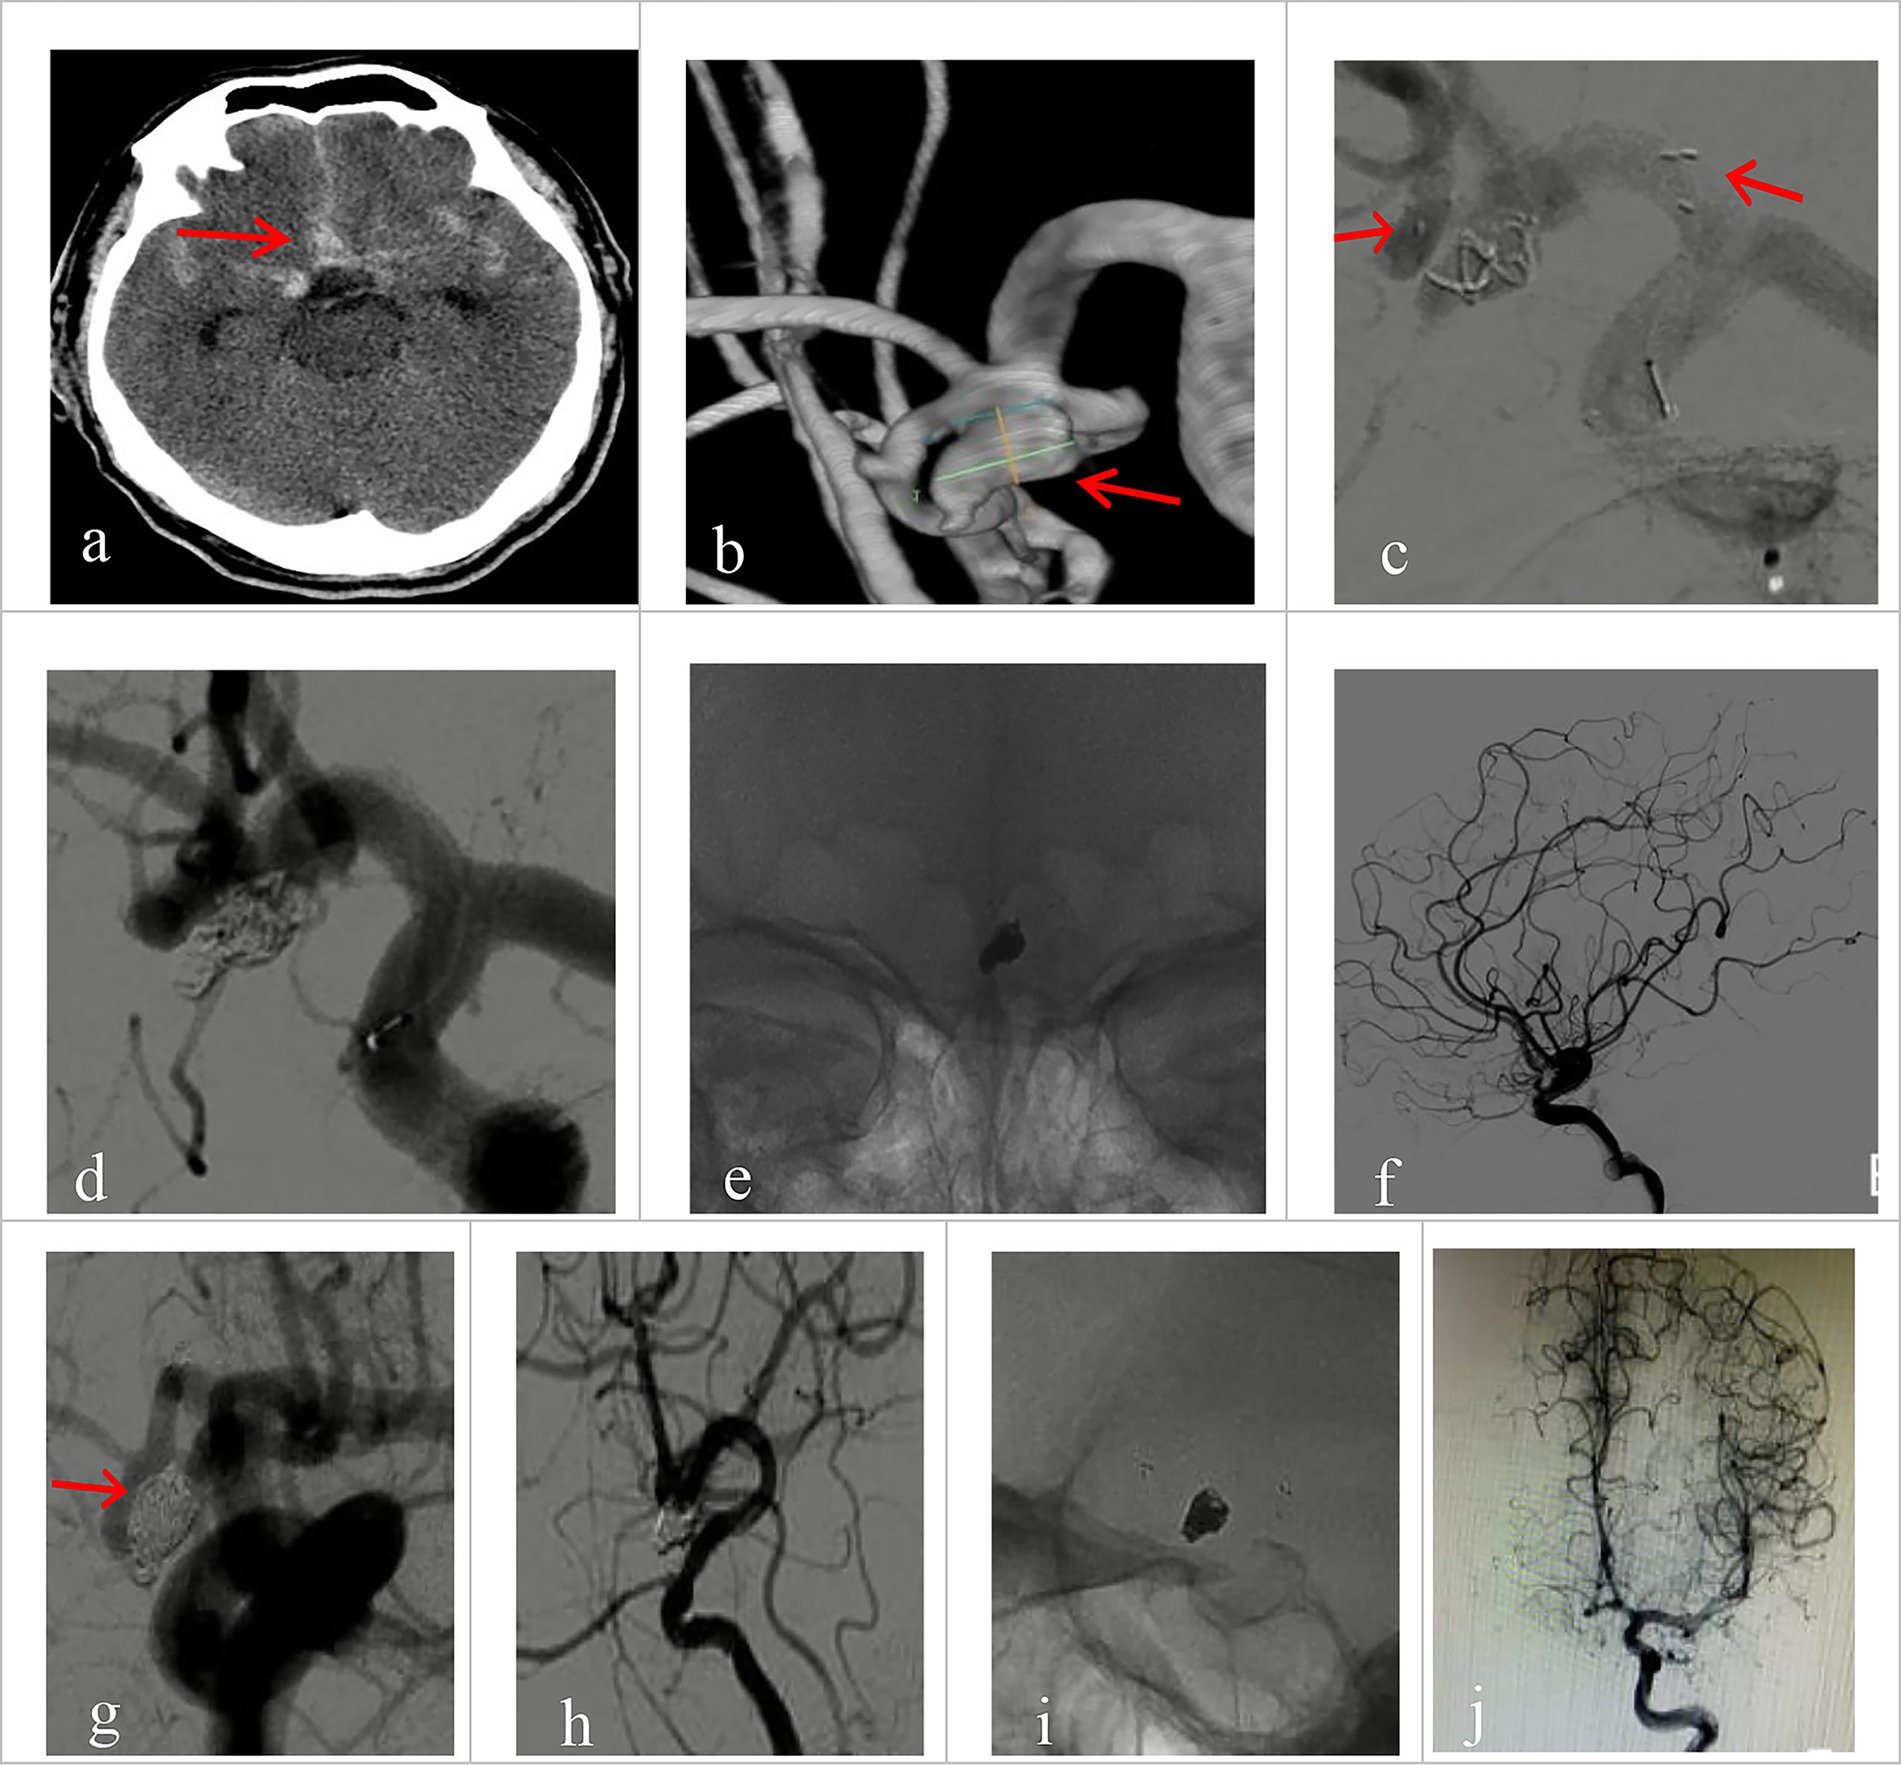

All 30 patients had effective Neuroform Atlas stent deployments, with good expansion and location. Twenty-three cases (76.7%) employed the double micro catheter approach, whereas 7 cases (23.3%) employed the single micro catheter technique. Immediate postprocedural angiography showed complete occlusion (RR Grade I) in 18 patients (94.7%) (Figure 1 shows the representative case), neck remnant (RR Grade II) in 0 (0%), and partial occlusion (RR Grade III) in 1 (5.3%). The data of the other 11 patients was unavailable because they refused to accept postprocedural angiography whose follow-up outcomes were good (mRS score ≤2). Clinical outcome was favorable in 29 patients (96.7%) and poor in 1 (3.3%). The mRS score was 3 in the single patient with poor clinical outcomes. Postprocedural angiographic and clinical outcomes are shown in Table 2 and Supplementary Figure 1. Procedure-related complications occurred in three patients (10%), including two cases of hemorrhagic complication and one case of thrombotic complication. No procedure-related death occurred. Contrast medium leakage was discovered during coil delivery in two patients with hemorrhagic complications, but it vanished during the angiography examination following rapid coil delivery. In terms of neurological recovery, mRS score was ≤2 (Figure 2 shows the representative case). One case was found post-procedural acute intrastent thrombosis. With slow injection of tirofiban hydrochloride (0.2 mL/kg) through the guiding catheter, angiography showed disappearance of thrombosis with effective reperfusion and neurological recovery, that was, mRS score ≤2. Postprocedural CT scan showed all patients had satisfactory embolization before smooth discharge from the hospital (Figure 3).

Figure 1. Imaging data of patients with ruptured wide-necked anterior communicating artery (ACoA) aneurysm treated with Neuroform Atlas assisted coiling (dual catheter system). (a) Preprocedural head CT showed spontaneous subarachnoid hemorrhage (red arrowhead). (b) Preprocedural DSA angiography with 3D reconstruction showed the location of a wide-necked ACoA aneurysm (red arrowhead). (c) The stent was positioned as planned and was accurately deployed during the procedure. The left red arrowhead indicates the proximal end of the stent, and the right arrowhead indicates the distal end. (d) The coil was delivered after the stent was deployed. (e) The stent maintained its expansion after coiling. (f) Immediate post-operative angiography (lateral view) demonstrated good patency of the aneurysm-bearing artery and its branch vessels without deficits. (g–j) Immediate angiography control showed that the aneurysm was completely embolized (Raymond Grade I), with sound patency of the stent, free of thrombosis. Vessels at all grades had good filling. (g) No coil compression 6 month after the procedure was seen on angiography at working projection (red arrowhead indicates the neck of the aneurysm). (h) Satisfactory embolization of the aneurysm with no recurrence, no contrast agent stagnation, no thrombosis in the stent. (i) Good expansion of the stent on 3D rotating view, without coil compression. (j) Parent vessel and its branches had normal fill.